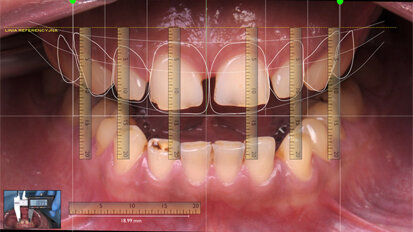

Nový úsměv za jeden den

Čt. 28. května 2020